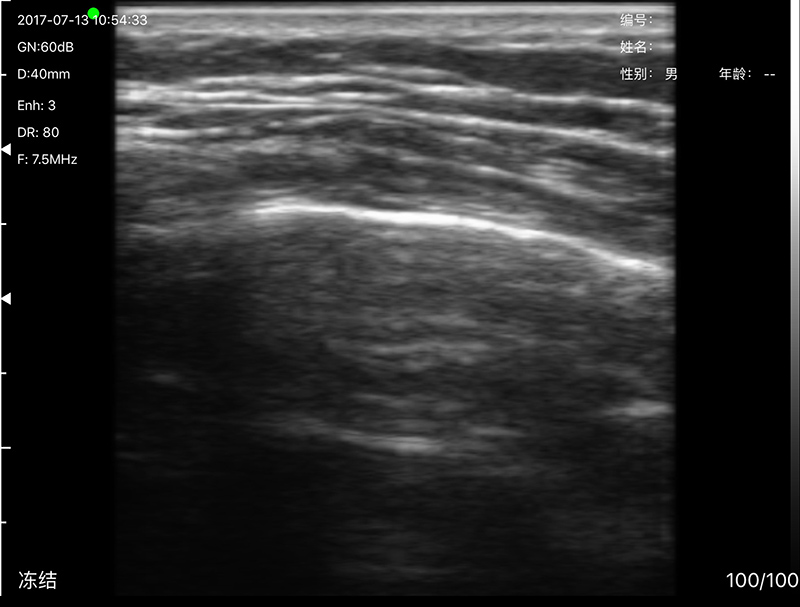

• 探头频率:微凸5.0/7.0MHz,高频线阵10/12 MHz

• 扫描深度:微凸60-160mm,高频线阵 20-80mm,可调

• 扫描角度和宽度:微凸R20,线阵L40